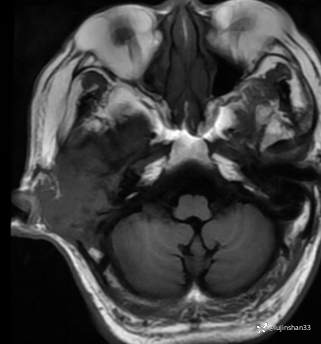

简要病史:患者2022年10月掏耳后出现右耳疼痛,流水,伴血性分泌物,伴听力下降,无头痛头晕,无口角歪斜,自行购买滴耳液及口服罗红霉素,效果不佳。后右耳痛加剧,偶需止疼药治疗。后于XXXXXX医院行中耳乳突CT检查示“右耳恶性肿瘤?坏死性外耳道炎?”颅脑磁共振平扫示“脑内多发缺血灶、梗塞灶,脑白质疏松,脑萎缩、右中耳恶性占位。”建议上级医院治疗。2023-4-13就诊于我科门诊,行右外耳道病理活检示“鳞状上皮黏膜慢性炎伴急性炎,可见较多炎性坏死,部分上皮增生明显伴不典型增生,小灶上皮呈重度异型增生伴癌变。”建议手术治疗。今患者为求进一步诊治,门诊以“颞骨占位(右)“收治入院。

MRI:

右侧颞骨鳞癌(T4)